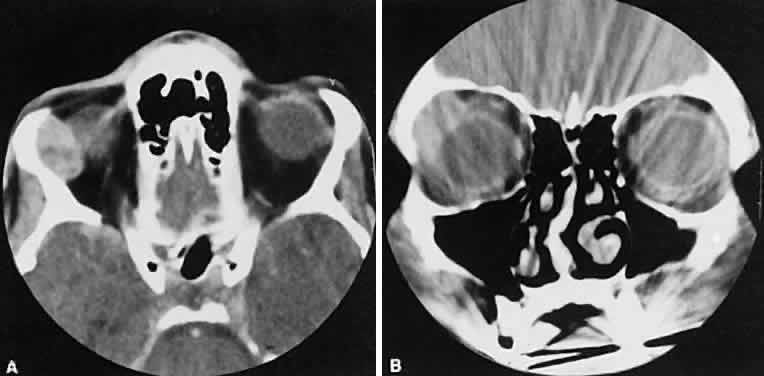

granulomatosis, or other vasculitic conditions. The CT characteristics of each subgroup are different and are considered separately. The nonspecific inflammation, if diffuse and acute, can affect the entire orbit with an amorphous infiltrate, which enhances with contrast (Fig. 4).13,14 The inflammation has been reported on occasion to spill over into the nasal15–18 and intracranial compartments.19–29 Chronic inflammation also may appear dense and relatively homogeneous. The margins may or may not be regular, and the lesions usually enhance with contrast. Changes in the adjacent bone, either sclerosis or hyperostosis or both, were seen on the CT in 30 (17%) of 176 patients with biopsy-proven pseudotumor.30

The CT evaluation of orbital myositis may show diffuse irregular enlargement of one or more EOMs; enlargement can be bilateral (Fig. 5). Incontradistinction to Graves' orbitopathy, involvement of the tendinous insertion and edema ofthe adjacent fat may be noted. Other conditions associated with EOM enlargement are listed in Table 2.31–33